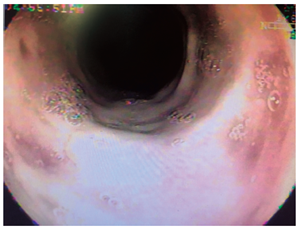

Varón de 76 años, que fue remitido por consultar por dolor intenso en el hipocondrio derecho, de tres días de evolución, malestar general, astenia y adinamia. Al examen estaba adolorido, taquicárdico, taquipneico, afebril, ictérico, con tirajes intercostales, estertores en base derecha y signo de Murphy positivo. Antecedente de diabetes mellitus tipo 2 e hipertensión arterial. Con diagnósticos de neumonía basal derecha, septicemia, trombocitopenia, hipertrofia prostática benigna, insuficiencia renal crónica agudizada, colelitiasis con dilatación de la vía biliar y colédocolitiasis. Durante la ultrasonografía endoscópica, como hallazgo incidental se describe mucosa esofágica negra en su totalidad, recubierta de exudado mucoso, sin erosiones, úlceras ni estrechez, con mucosa por debajo de la línea Z de aspecto usual. La videoendoscopia demuestra ulceración esofágica desde los 21 cm de la arcada dentaria, que se torna circunferencial a los 23 cm, recubierta por fibrina, aspecto negro y grisáceo desde los 27 cm hasta la unión cardioesofágica (Figuras 5, 6 y 7), respetando la mucosa cardial (Figura 8). La colangiopancreatografía retrógrada endoscópica (CPRE) demuestra vía biliar extrahepática dilatada con defecto de llenado en el tercio medio y distal; se practica esfinterotomía pequeña (por trombocitopenia de 31 000 x mm3) (Figura 9) y se extraen cálculos pequeños con balón, dejando un stent plástico de 7 Fr x 7 cm, con drenaje de bilis clara con microcálculos. El paciente evoluciona satisfactoriamente y sale del hospital con resolución del cuadro doloroso e ictérico. A las 10 semanas se encuentra asintomático, sin aceptar la realización de procedimientos de control.

Los hallazgos endoscópicos son diversos y requieren que se descarten otras etiologías que producen alteraciones similares, como la ingestión de cáusticos, otros tóxicos o carbón, infecciones, radioterapia o melanoma metastásico, entre otros 3,10. Los hallazgos pueden ir desde membranas blanquecinas, que al removerlas dejan una mucosa grisácea o negruzca, hasta necrosis difusa con exudados amarillentos adherentes, ulceración en la mayoría y aspecto negruzco o grisáceo, demarcado por la unión gastroesofágica, con región cardial de aspecto usual, como se describen en nuestros casos. El espectro de lesiones asociadas es amplio, como hemorragia gástrica o duodenal, ulceraciones y perforaciones, representadas en la casuística general con úlceras duodenales (10; 4 %), gástricas (2; 1 %), necrosis isquémica duodenal (2; 1%); sangrado activo (4; 2 %), perforación esofágica (3; 1,3 %) y duodenal (1; 0,5 %) (Tabla 1).